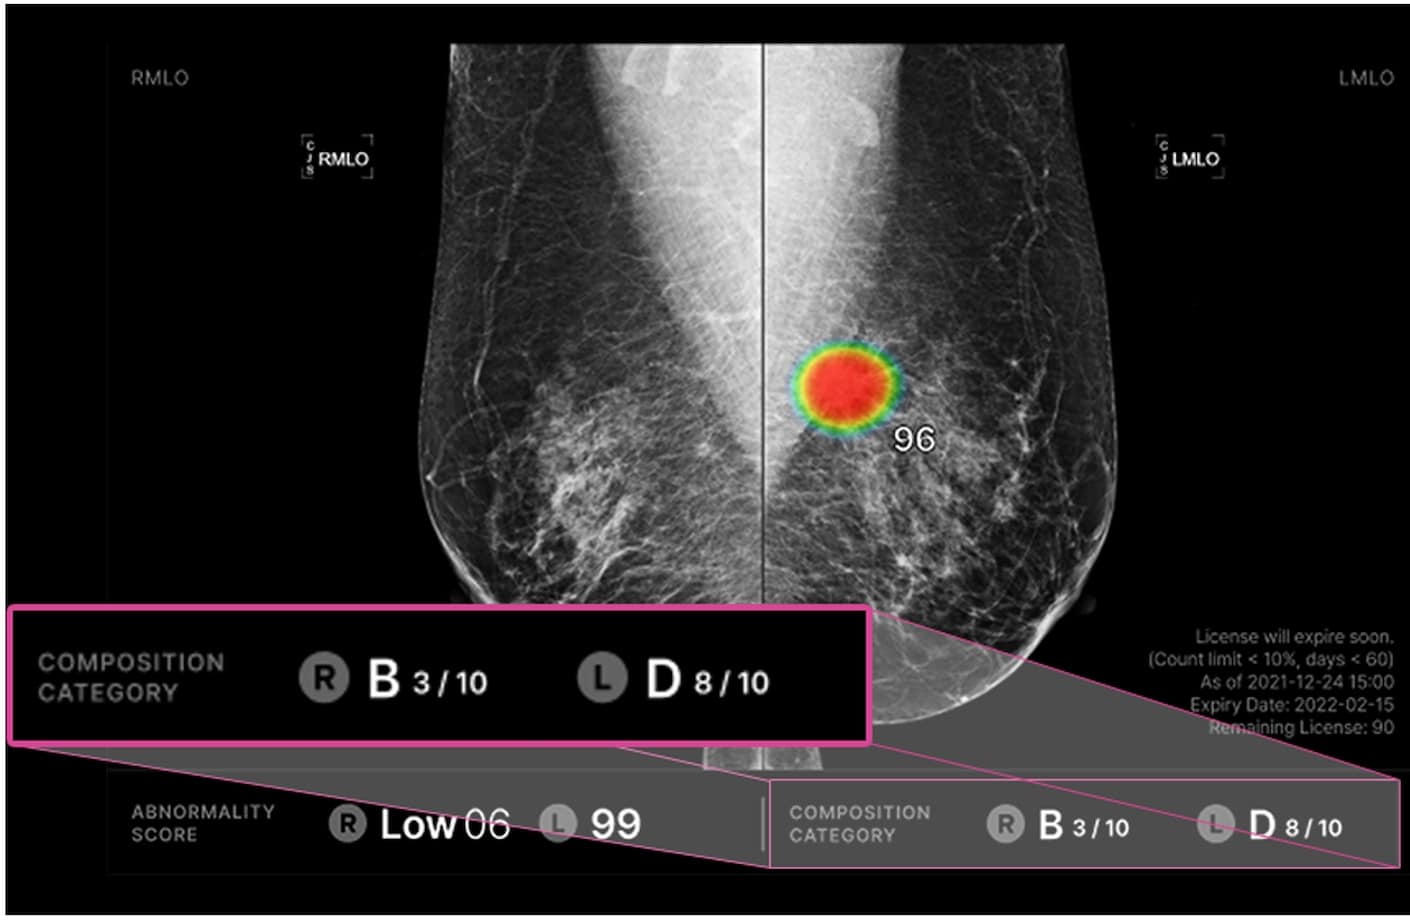

루닛 인사이트 MMG는 유방 촬영 영상을 분석해 유방암 의심부위의 위치와 유방 내 병변이 존재할 가능성을 0~100 범위의 점수로 표시합니다.

루닛 인사이트 MMG는 유방 치밀도1를 자동으로 분석합니다. BIRADS 유방밀도 A, B, C, D와 함께 각 밀도에 해당되는 AI 유방치밀도 점수(1-10)을 표시해 세분화된 분석이 가능합니다.